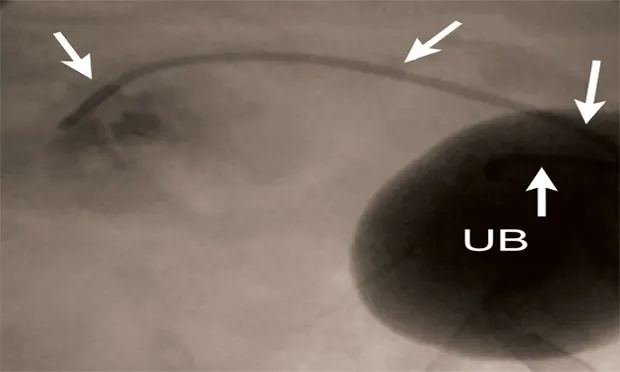

Figure 5A: Serial lateral fluoroscopic images of a dog with ureteral obstruction secondary to trigonal transitional cell carcinoma.

Ultrasound-guided 18-gauge needle access into the renal pelvis with subsequent contrast ureteropyelogram demonstrating hydronephrosis and hydroureter (white arrows). A colonic marker catheter (black arrows) aids in radiographic magnification and stent length determination.

Similar techniques are currently being employed to manage ureteral obstructions secondary to uroliths, strictures, or malignancies (Figure 5). These procedures can be performed surgically or with minimal invasiveness (percutaneously or via cystoscopy) to reduce morbidity and improve outcomes in cats and dogs.9 For example, dogs with ureteral obstructions can now be treated through a small needle stick through the flank or endoscopically to relieve the obstruction and be discharged on an outpatient basis.

Currently, minimally invasive image-guided procedures can be performed on an outpatient basis to relieve these obstructions, provide urine drainage, improve patient comfort and renal function, and permit ongoing or subsequent chemotherapy administration to limit tumor growth and spread instead of simply euthanizing patients with malignant urinary tract obstructions.